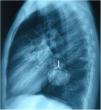

A 17 years old male presented with cough. Posteroanterior and lateraly direct radiography showed cavitary lesion in the middle zone and “moonsign” in the lower zone of the right lung (Figs. 1 and 2). The patient underwent right thoracotomy. Cystotomy and capitonnage was performed to hydatid cyst.

Fig. 1.

Moon sign is seen on the posteroanterior chest X-ray (arrow).

Radiologically, there are many radiological signs associated with the hydatid cyst.1,2 Moon sign is seen when air enters between the pericyst and endocyst. This finding indicates that the hydatid cyst will rupture. Radiological findings have an important role in the diagnosis of pulmonary hydatid cyst.